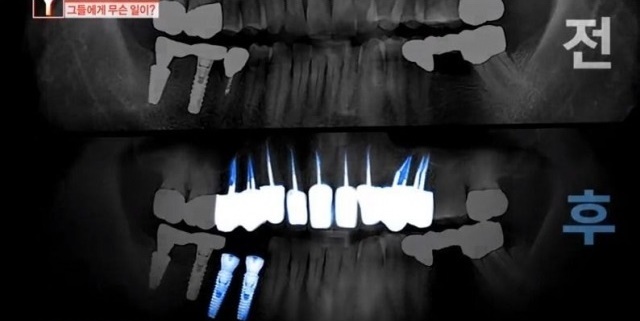

그는 치아에 생긴 얼룩만 지우고 싶었는데 치과의 원장은 윗니에 충치가 조금씩 있다며 잇몸마취 상태로 윗니 10개를 마음대로 갈아버렸다고 한다.

피해자의 치아 상태를 살펴본 다른 치과 전문의는 “충치가 확실하지 않고 충치가 없었다고 보이는데 (윗니를) 많이 갈아버린 것”이라며 “(의사가 한) 행위 자체로만 보면 상해다”라고 목소리를 높였다.